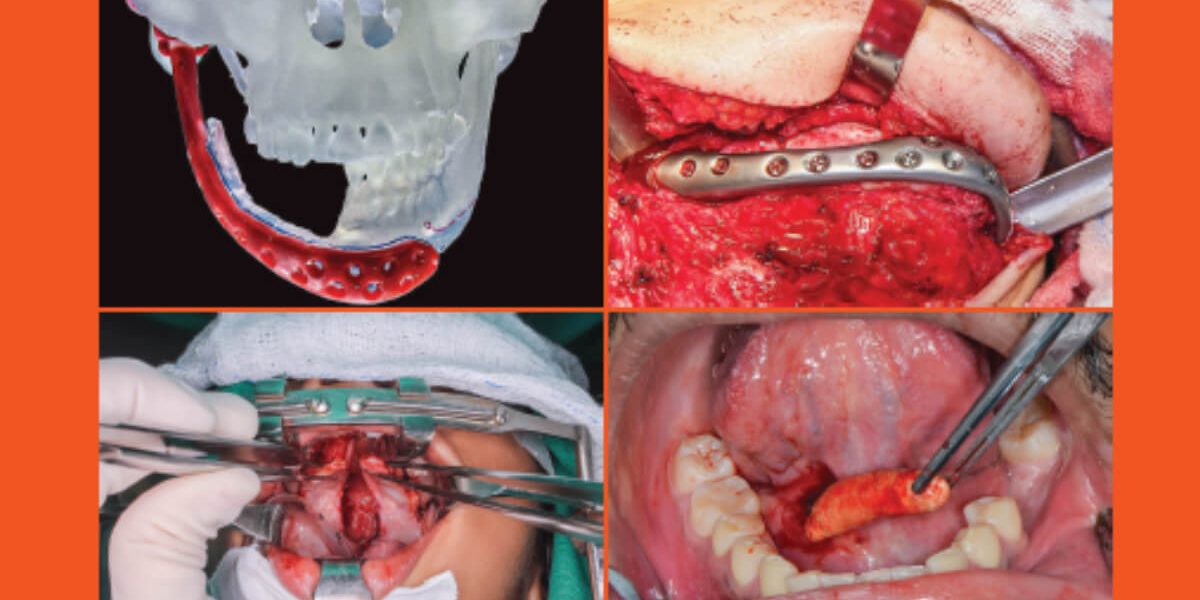

Journal of the Brazilian: College of Oral and Maxillofacial Surgery

Volume 07  |  Number 2  |  August 2021